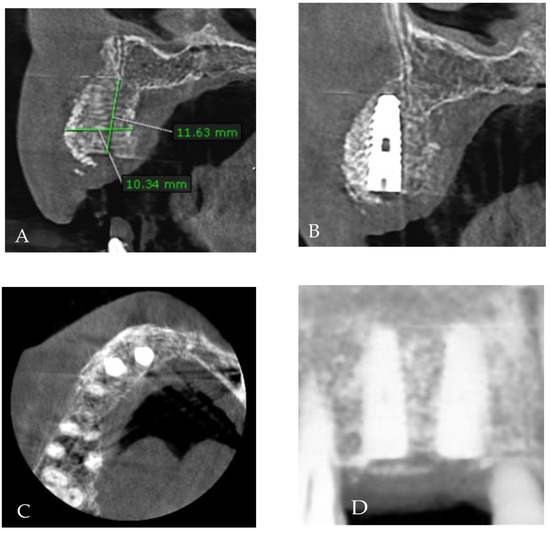

Customized 3D-Printed Titanium Mesh Developed for an Aesthetic Zone to Regenerate a Complex Bone Defect Resulting after a Deficient Odontectomy: A Case Report

Background and Objectives: Alveolar ridge augmentation in the complex bone defect is a popular topic in implantology. Guided bone regeneration (GBR) is one of the most commonly applied methods to reconstruct alveolar bone. The application of a membrane is the fundamental principle of GBR. There are many membrane types used in oral surgery, but the advantage of the titanium mesh is the rigidity which provides space maintenance and prevents contour collapse. The smooth surface also reduces bacterial contamination. Using computer-aided design (CAD) and computer-aided manufacturing (CAM) in dentistry allows us to obtain the perfect architecture form of the mesh, which covers and protects the bone reconstruction. Case presentation: We present a surgical case of a 27-year-old female patient with severe aesthetic bone atrophy after a deficient odontectomy. Based on the GBR clinical applications, the technique consists of bone reconstruction and a customized titanium mesh application. Using mesh titanium in this case presentation was a reliable alternative to perform a lateral alveolar bone augmentation and reconstruct ridge deformities before reaching an ideal implant placement. Conclusions: According to our case report, the customized titanium mesh could be a valuable option for guided bone regeneration in aesthetic maxillary defects. Full article